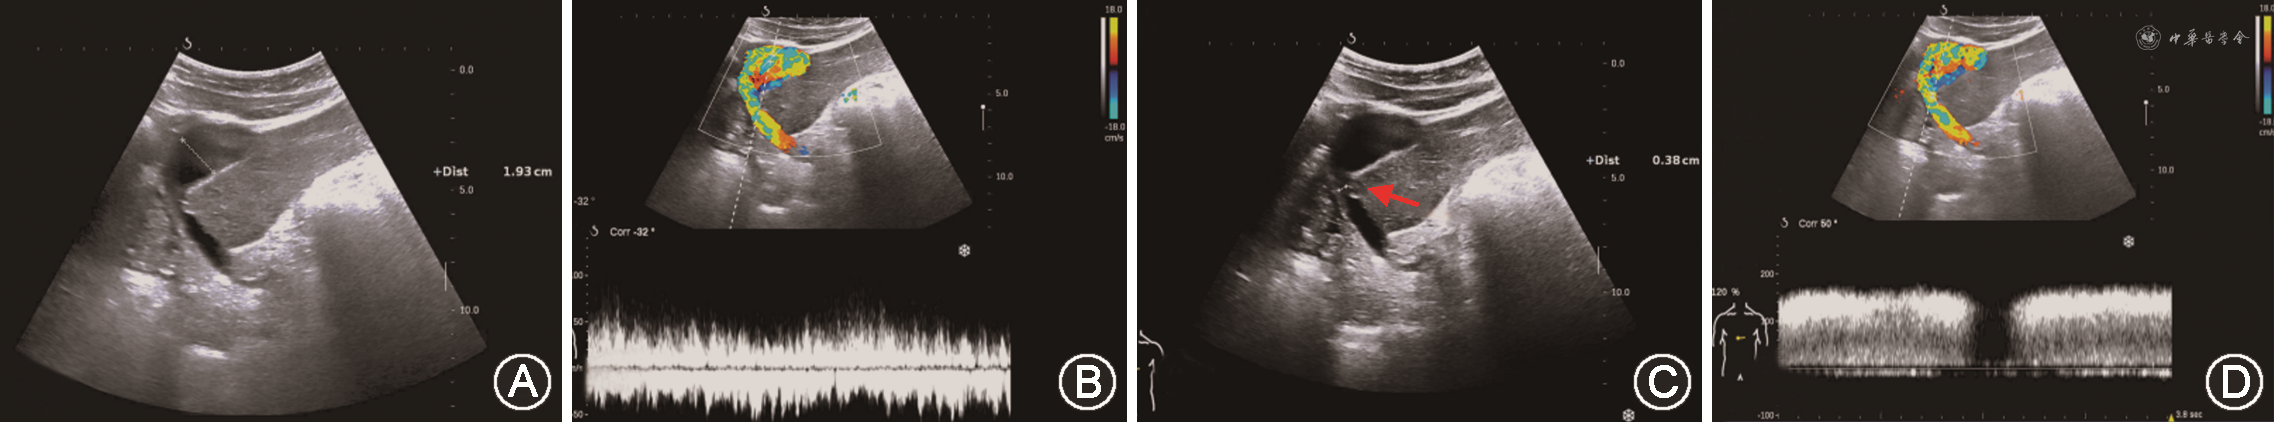

(1)PVT:PVT多发生于肝外门静脉段或门静脉吻合口。肝移植前受体有PVT病史、门静脉内径较细(<5 mm)、患者处于高凝状态及有脾切除手术病史等是好发因素[47,51,71]。移植肝PVT声像图表现为门静脉管腔内见实质回声,CDFI显示血流充盈缺损或不能测及彩色血流。急性PVT灰阶超声上有时可呈无回声表现,需结合CDFI检查进行鉴别。当CDFI检查门静脉血流显示不清时,应用超声造影可以改善门静脉的显示,明确门静脉是否闭塞(图17)[33,72]。

(2)PVS:移植肝PVS多发生在门静脉吻合口附近[73]。超声诊断PVS形态学依据是门静脉内径减少大于50%[74]。血流动力学依据包括:①门静脉吻合口处流速>125 cm/s[44];②门静脉吻合口处与之前正常段流速比值>3[74, 75]。以跨门静脉吻合口的两端流速差值>60 cm/s诊断门静脉显著狭窄,灵敏度可达100%,特异度为84%[76]。移植肝供受体门静脉内径不匹配时,CDFI检查门静脉有时可见湍流,应注意与PVS鉴别(图18)[77]。当门静脉吻合口处内径小于5 mm时,为防止移植肝预后不良,需及时进行介入手术或外科治疗[74]。

(1)肝静脉或下腔静脉狭窄:肝静脉或下腔静脉狭窄多发生在吻合口,常见原因与外科吻合技术有关。声像图表现为:灰阶超声显示静脉吻合处细窄,CDFI局部可见彩色混叠及流速增高,当狭窄处与狭窄前正常段流速比值>3~4时,提示显著狭窄。有研究指出,当观察到移植肝静脉持续为单相波且峰值流速<15.5 cm/s时,应高度警惕肝静脉狭窄可能;而肝静脉持续为双相或三相波时则基本可排除肝静脉显著狭窄[79, 80]。需注意,以肝静脉内持续单相波频谱诊断HOO灵敏度高,但特异度低。移植术后早期移植肝肿大,肝外积液(血)压迫,移植肝静脉内也可出现类似频谱[1]。

(2)肝静脉或下腔静脉血栓:肝静脉或下腔静脉血栓与外科吻合技术及患者处于高凝状态均有关。声像图表现为肝静脉或下腔静脉附壁见实质回声,CDFI示局部血流充盈缺损。增强CT或增强MRI可观察到静脉相应引流肝段的血流灌注改变。肝中静脉属支血栓闭塞时,静脉相应引流肝段血流灌注改变,超声造影检查可见受影响区域肝实质动脉期呈片状高增强,门静脉期消退为片状低回声。超声造影诊断肝中静脉属支血栓闭塞,假阳性率从CDFI诊断时的14%下降为3%[81]。需注意,术式如果为“背驮式”肝移植,其静脉吻合的盲端处常可见血栓形成,该血栓通常无不良临床后果。